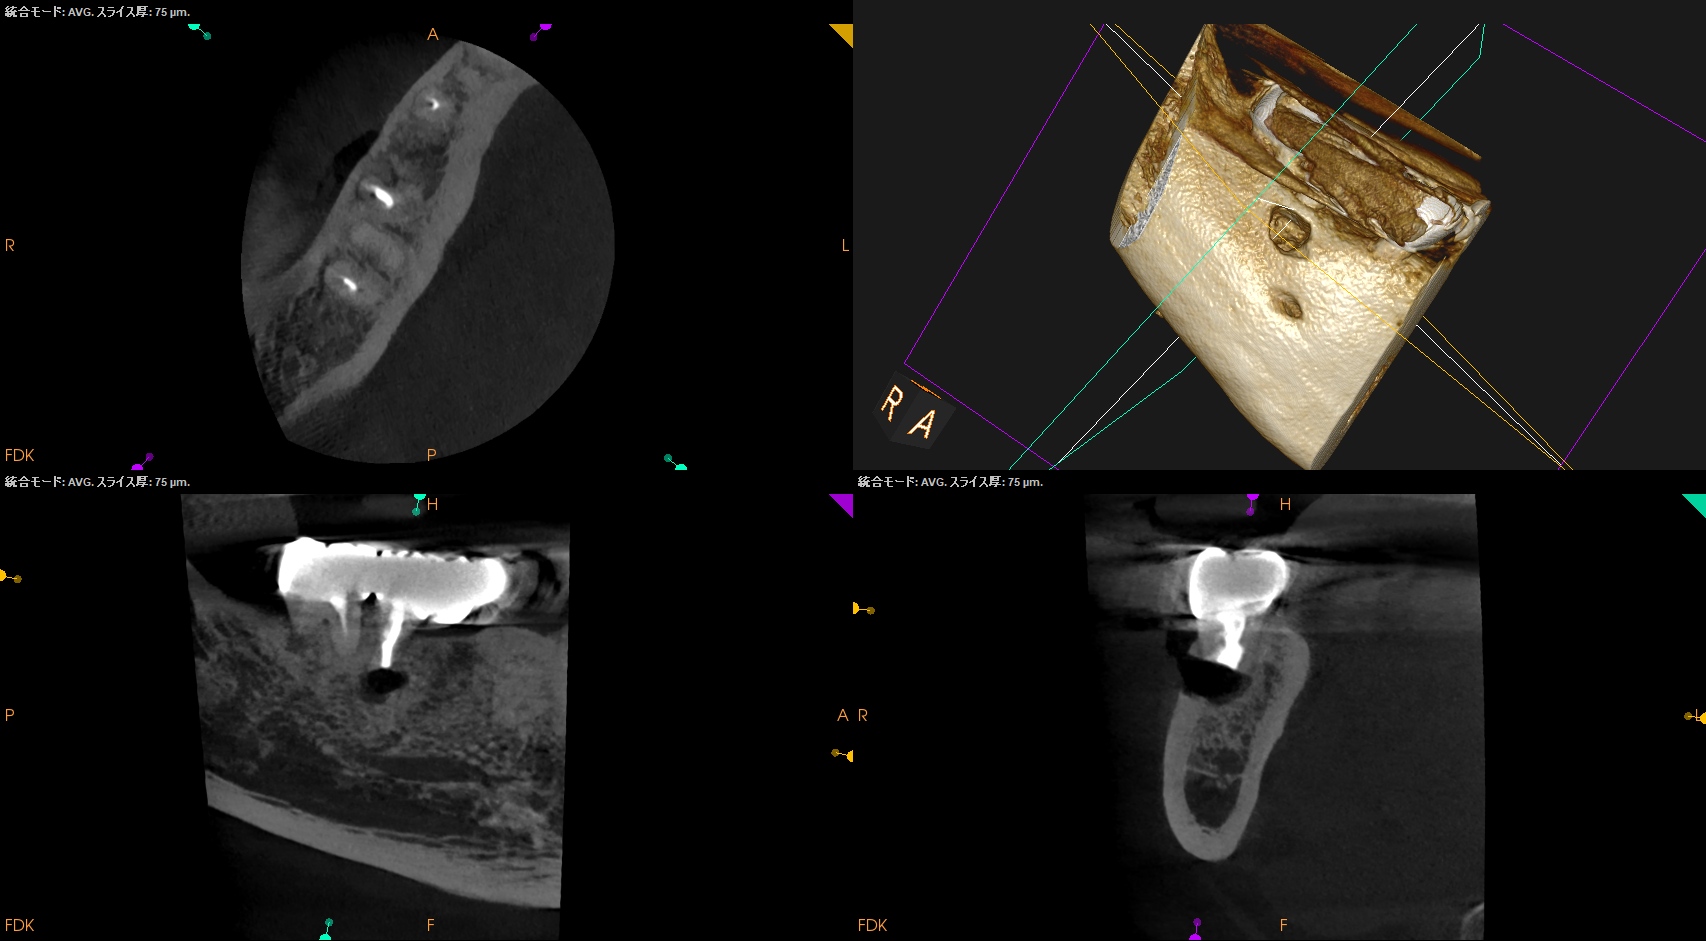

過日、#30 D Apicoectomyがあったときのことだ。

頬側の歯槽骨を厚く(3mm), Osteotomyしなければならない。

当該部位をOsteotomyするが…

3mm削合してもApexが出てこなかった。